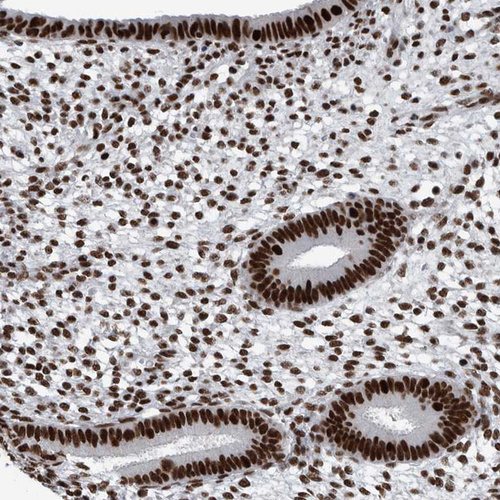

Immunohistochemical staining of human lymph node shows strong nuclear positivity.